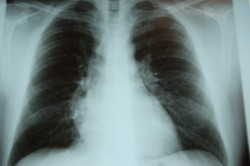

asbestos-disease-lungsCrane Co. was accused in an asbestos lung cancer lawsuit of failing to warn users of its products that they contained asbestos. It was this alleged asbestos exposure that caused a man who used the products during employment to develop lung cancer.

Many individuals have developed lung cancer after asbestos exposure. Many have experienced occupational asbestos exposure if they worked in the construction field, in a warehouse, or at a Navy yard.